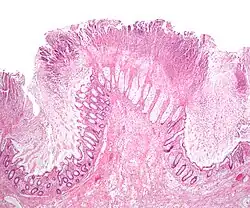

| Micrograph of pseudomembranous colitis, a cause of toxic megacolon. H&E stain. | |